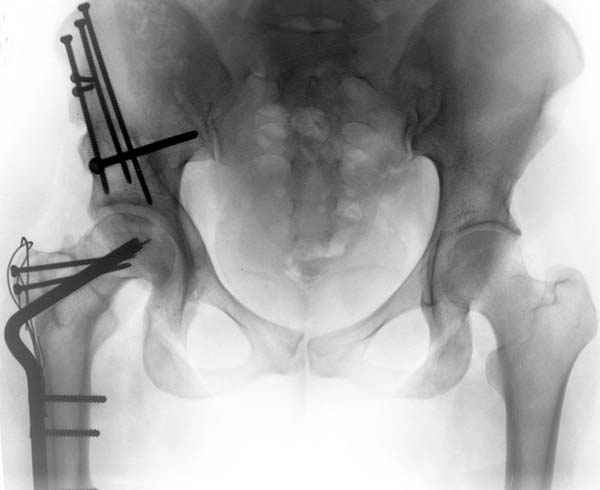

Рис.1 Трехмерная модель тазобедренного сустава с аналогом связки головки бедра. Заметно, что из торца головки выходит капроновый шнур, который с одной стороны прикрепляется к ножке бедренной части модели, а другой его конец, проходя через головку и прикрепляется к вертлужной части модели. Динамометр оказывается не нагруженным, так как аналог связки головки бедра замыкает подвижный узел модели во фронтальной плоскости.

|

Рис.2 Та же трехмерная модель тазобедренного сустава без аналога связки головки бедра. Пружина динамометра удерживает тазовую часть модели от опрокидывания, поддерживая стабильность так же, как отводящие мышцы обеспечивают ее в отсутствии связки головки бедра.